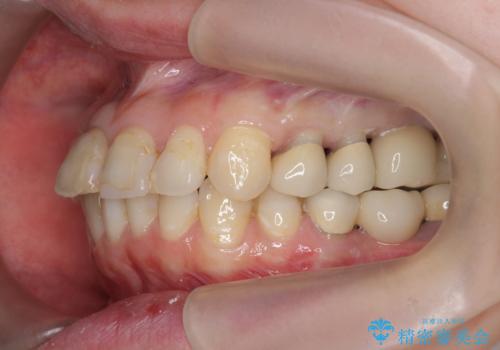

インプラント・セラミック・矯正治療を含む包括歯科診療

- 20代女性

- 矯正装置

- インビザライン

- 治療期間

- 3年

- 治療回数

- 30回以上

- 「地元の歯医者にずっと通っているが、どんどん歯が悪くなる。時間とお金がかかってもいいので徹底的に歯を治したい。」

、と総合的な歯科治療を希望されて来院されました。

虫歯や咬合関係・歯槽骨の吸収・根尖病変・歯の欠損・複合的な問題を一つずつ解決し、

安定した噛み合わせの構築・歯ブラシのしやすい環境の整備・歯内歯周の感染除去・造骨を伴うインプラント治療

を行い、長期的な予後を見込める口腔内環境を確立、整備して行きます。

- 440万円費用は治療当時の料金となります